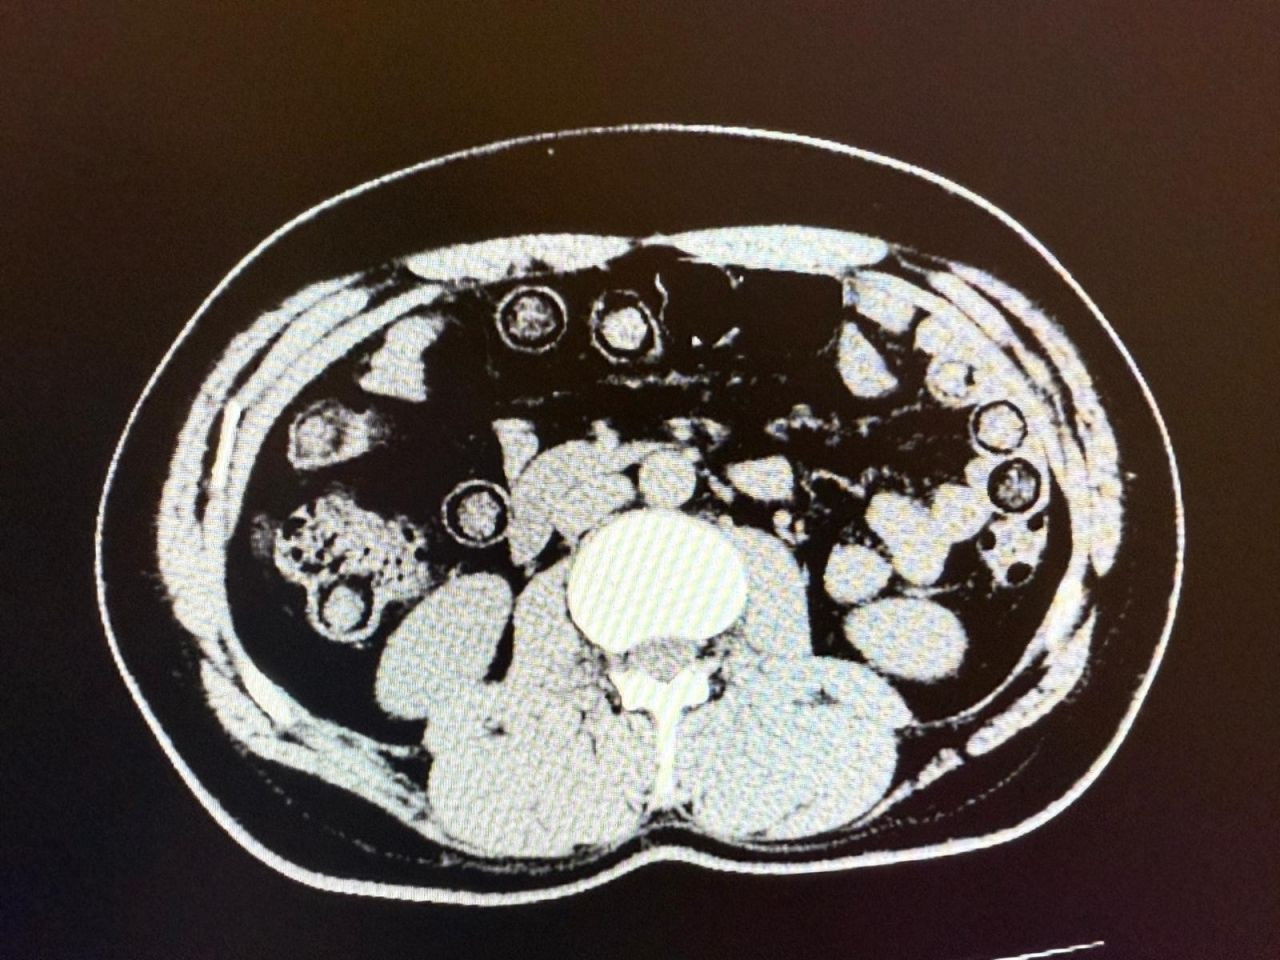

Hastanede yapılan tomografi görüntülerinde, şahısların midelerinde toplam 94 kapsül içinde 928 gram metamfetamin taşıdığı belirlendi. Kapsüller hastane ortamında çıkartılarak muhafaza altına alındı.